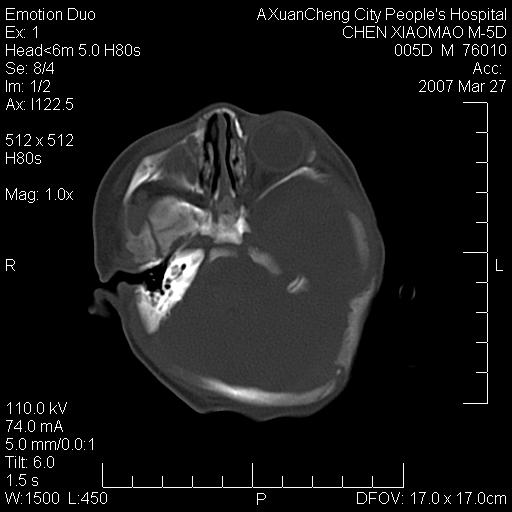

大家看看可有出血?另外枕骨中央是骨缝还是骨折

颅内未见明显异常。枕骨鳞部应为假缝(颅外软组织无肿胀),有外伤吗?

枕骨骨折可以下,应该比较明显,颅内还是正常的,不放心的话,短期随访。

未见明显异常,,那是横窦影,“缝”是后囟